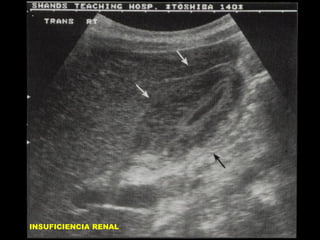

INSUFICIENCIA RENAL